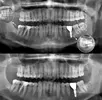

خراجات الفك